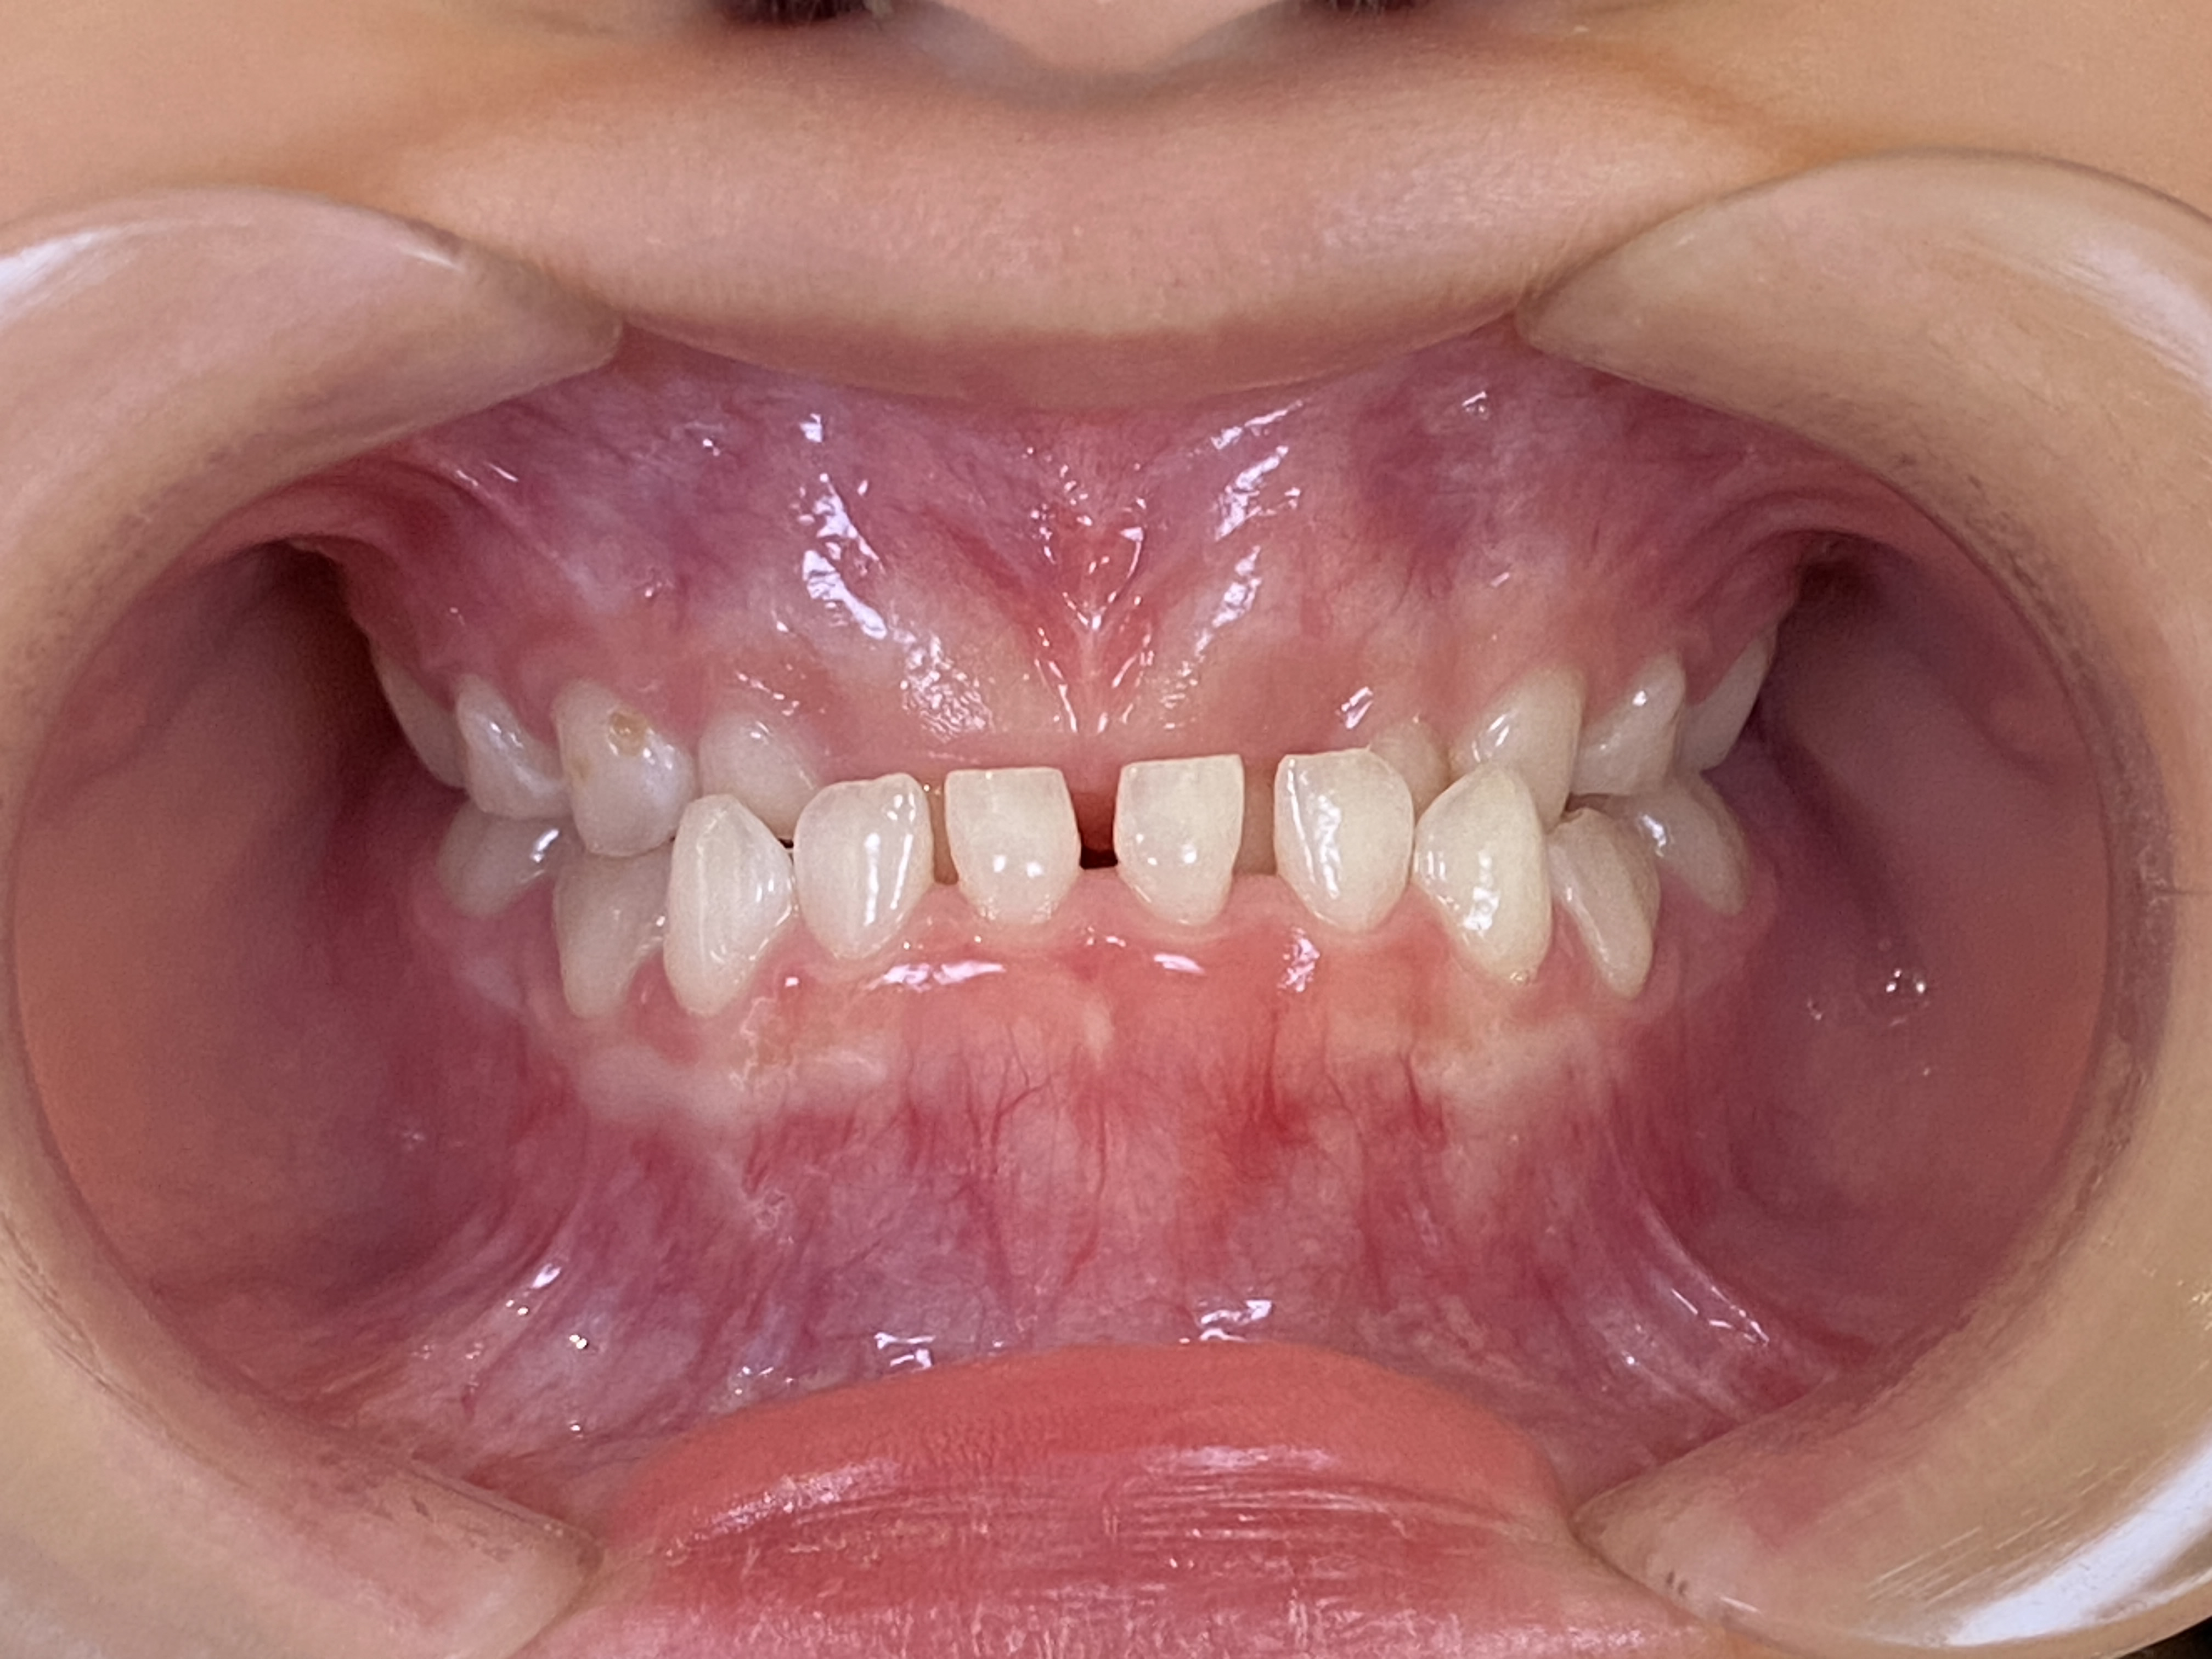

治療終了時(8歳5か月)

まだ、上の2番目の前歯は出てきている途中です。